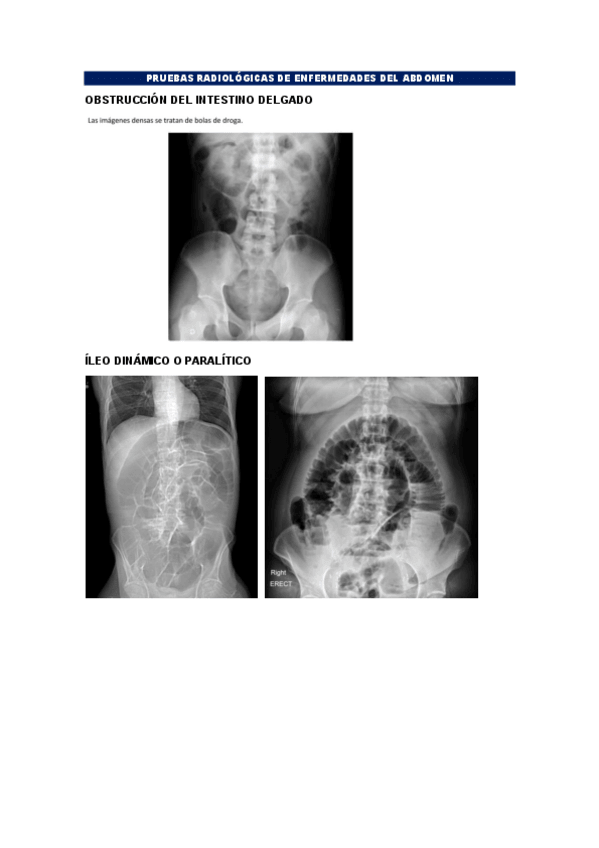

Ejemplos de RX, TC, RM de las enfermedades que hemos visto en clase o en prácticas. NO son fotos de clase ni de prácticas

BLOQUE-ABDOMEN.pdf